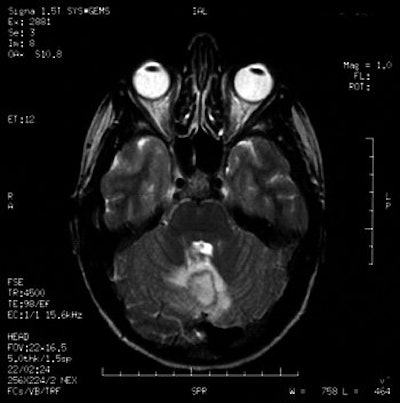

Gadolinium-enhanced MRI scans confirmed the presence of a cerebellar brain abscess in a 22-year-old woman who had undergone tongue piercing four weeks earlier. Images courtesy of Dr Richard Martinello.

Their patient presented with her symptoms four weeks after her tongue piercing. A neurological exam revealed that the patient was alert, and no abnormalities were found in cranial nerve, motor, or sensory function.

However, a brain CT scan revealed a "right cerebellar enhancing lesion with surrounding edema, and an MRI scan with gadolinium confirmed the presence of a solitary brain abscess," the authors reported. The patient underwent a right suboccipital craniotomy to drain the abscess and was then treated with antibiotics. A follow-up CT showed complete resolution of the abscess.